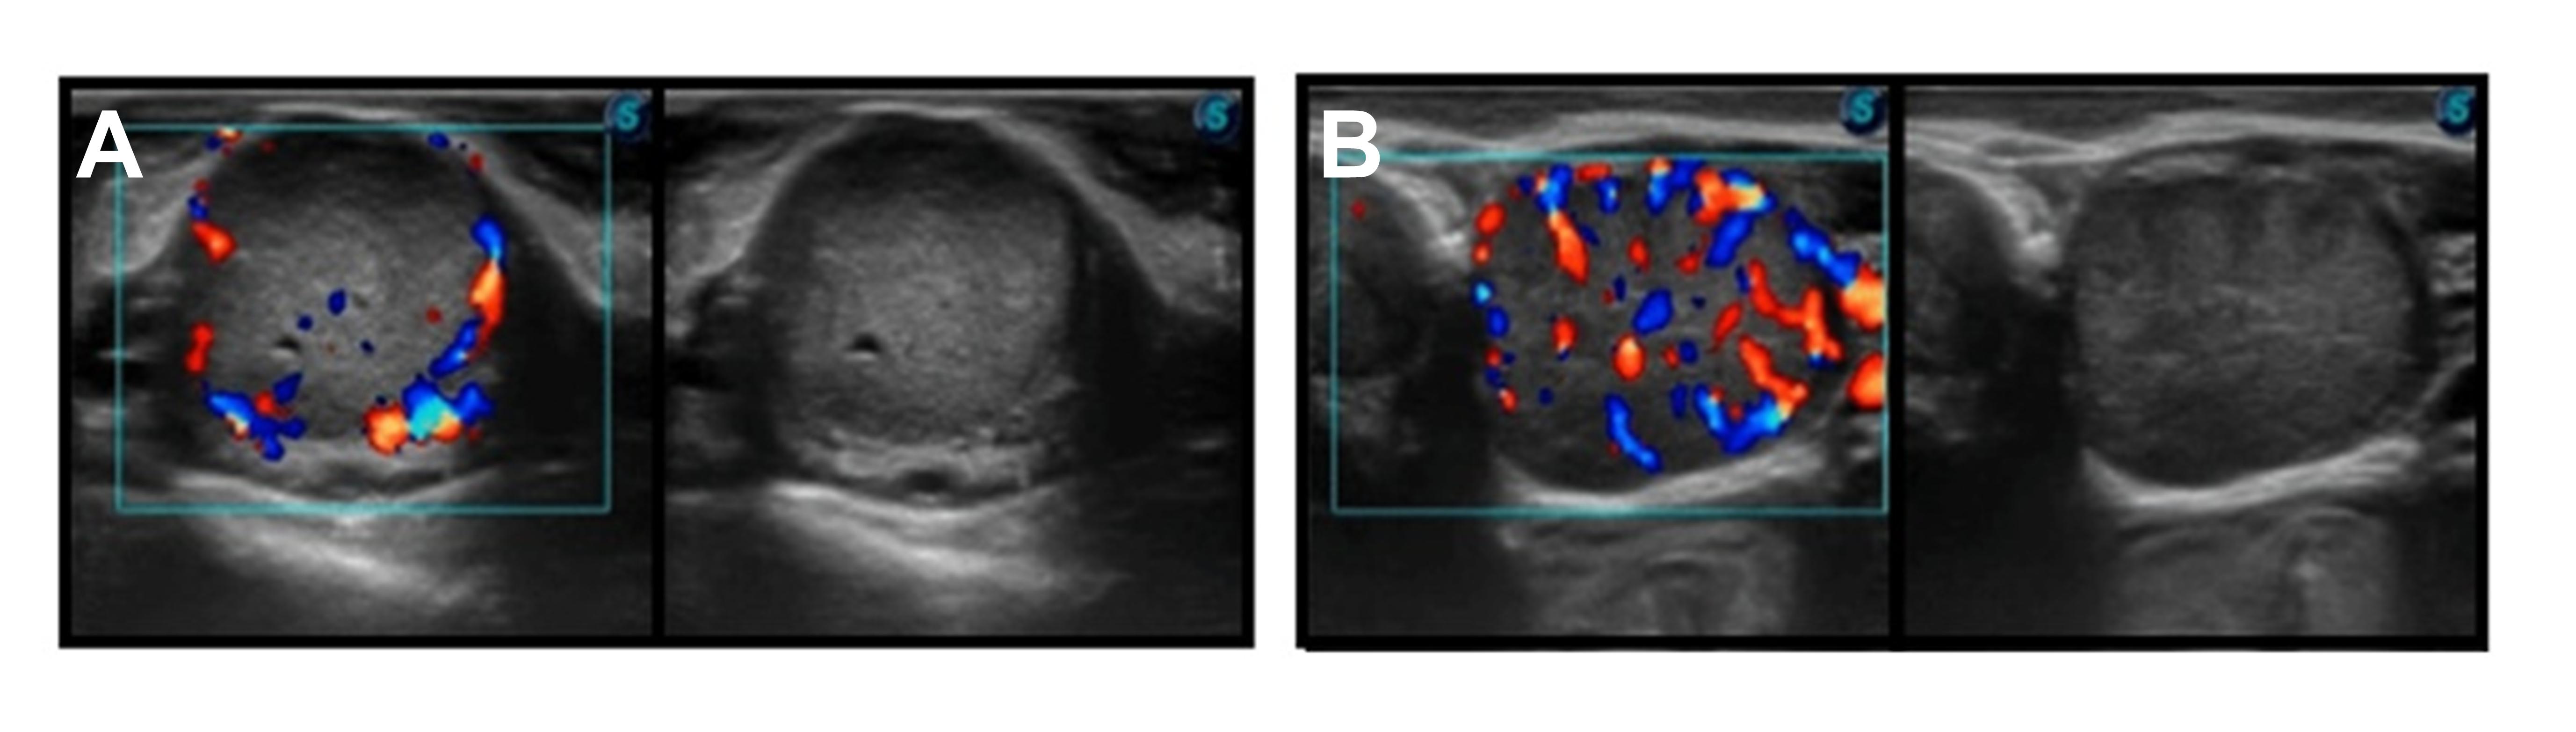

Emerging tools such as color Doppler ultrasonography offer additional insight into CL function. Unlike conventional ultrasound imaging, color Doppler evaluates blood perfusion within the CL. Greater blood perfusion is generally associated with greater luteal activity and progesterone production (Figure 2). Research evaluating luteal blood perfusion in embryo recipients has demonstrated cows with greater CL blood perfusion at the time of transfer achieved greater pregnancy rates than cows with minimal perfusion, even when CL size was similar (Figure 3).

FIG. 2: Representative color Doppler ultrasonography images of the corpus luteum (CL) at the time of embryo transfer. Panel A illustrates a CL with low blood perfusion, whereas Panel B demonstrates a CL with high blood perfusion. Color signals indicate vascular blood flow within the CL.